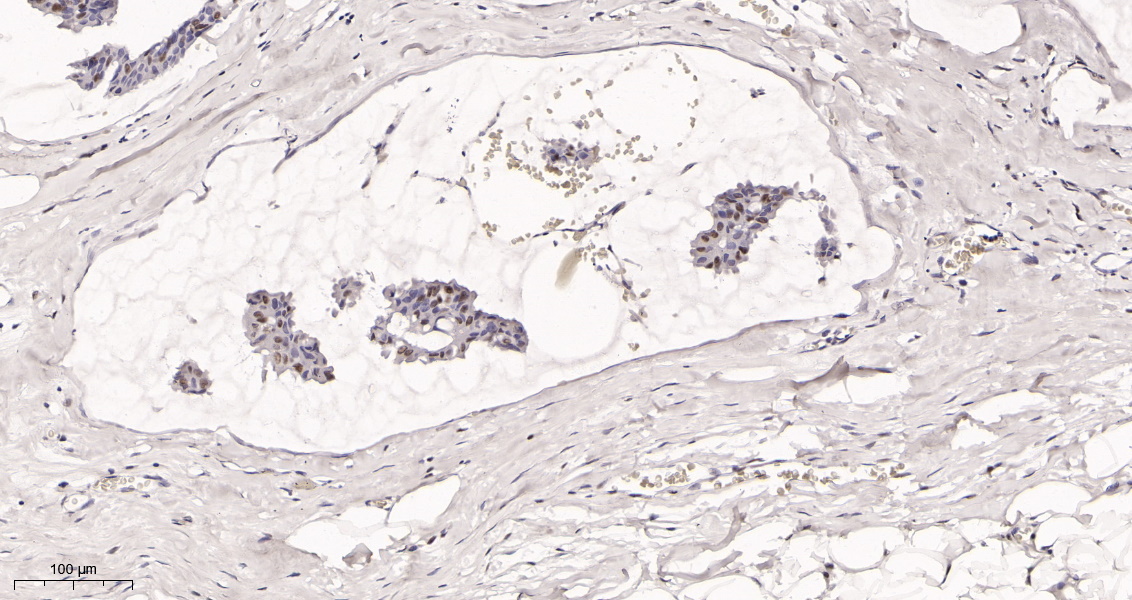

产品名称Rad21 (16H8) Rabbit Monoclonal Antibody

推荐应用WB,IHC-P,IF-P,IF-F,IF-ICC,IP,ELISA

稀释度IHC-P 1:200-1000,WB 1:1000-5000,IF-P/IF-F/IF-ICC 1:200-1000,ELISA 1:5000-20000,IP 1:50-200